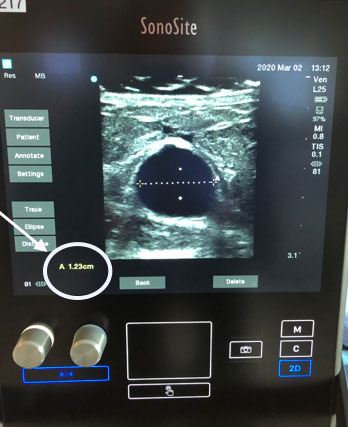

Dialysis Measuring the Vessel Graphic